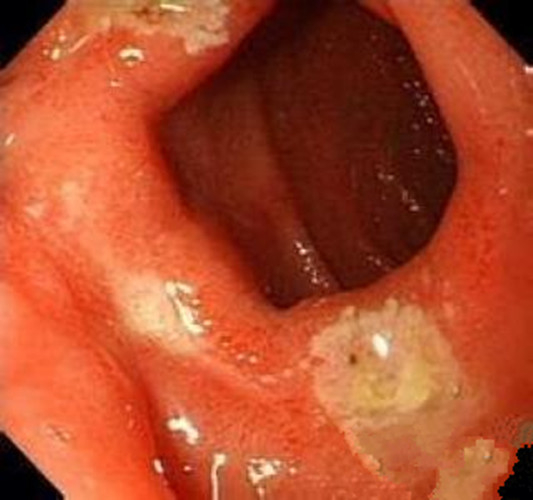

中型淺表萎縮慢性胃炎